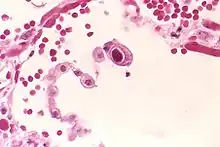

CMV infection can be demonstrated microscopically by the detection of intranuclear inclusion bodies. On H&E staining, the inclusion bodies stain dark pink and are called "owl's eye" inclusion bodies.[35]

| CMV infection of a human lung pneumocyte | |